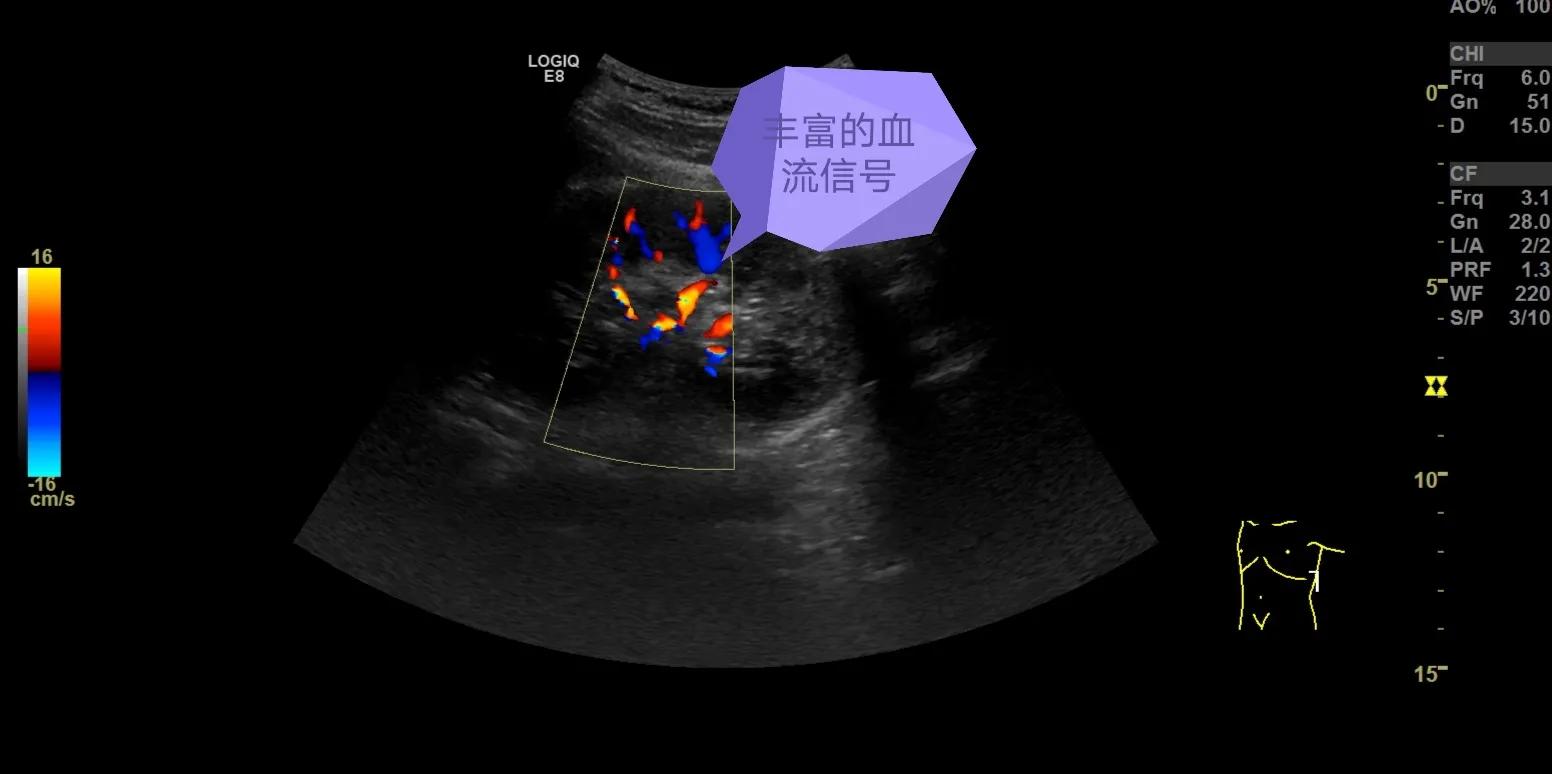

正常的肾脏血流非常丰富,呈树枝样分布。